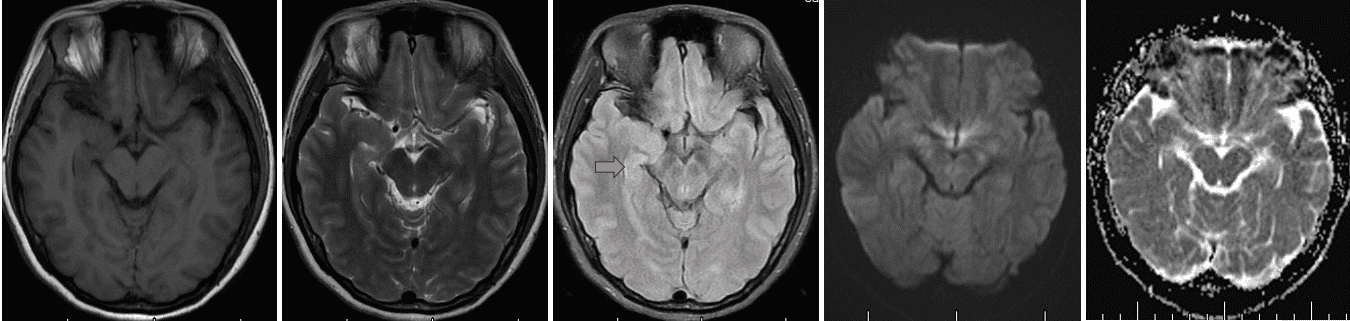

头MR(序列依次为T1、T2、Flair、DWI、MRA)未见异常,隔日复查MR强化,亦未见颅内异常强化灶。 仔细阅片,中脑层面右侧海马组织信号稍有增高